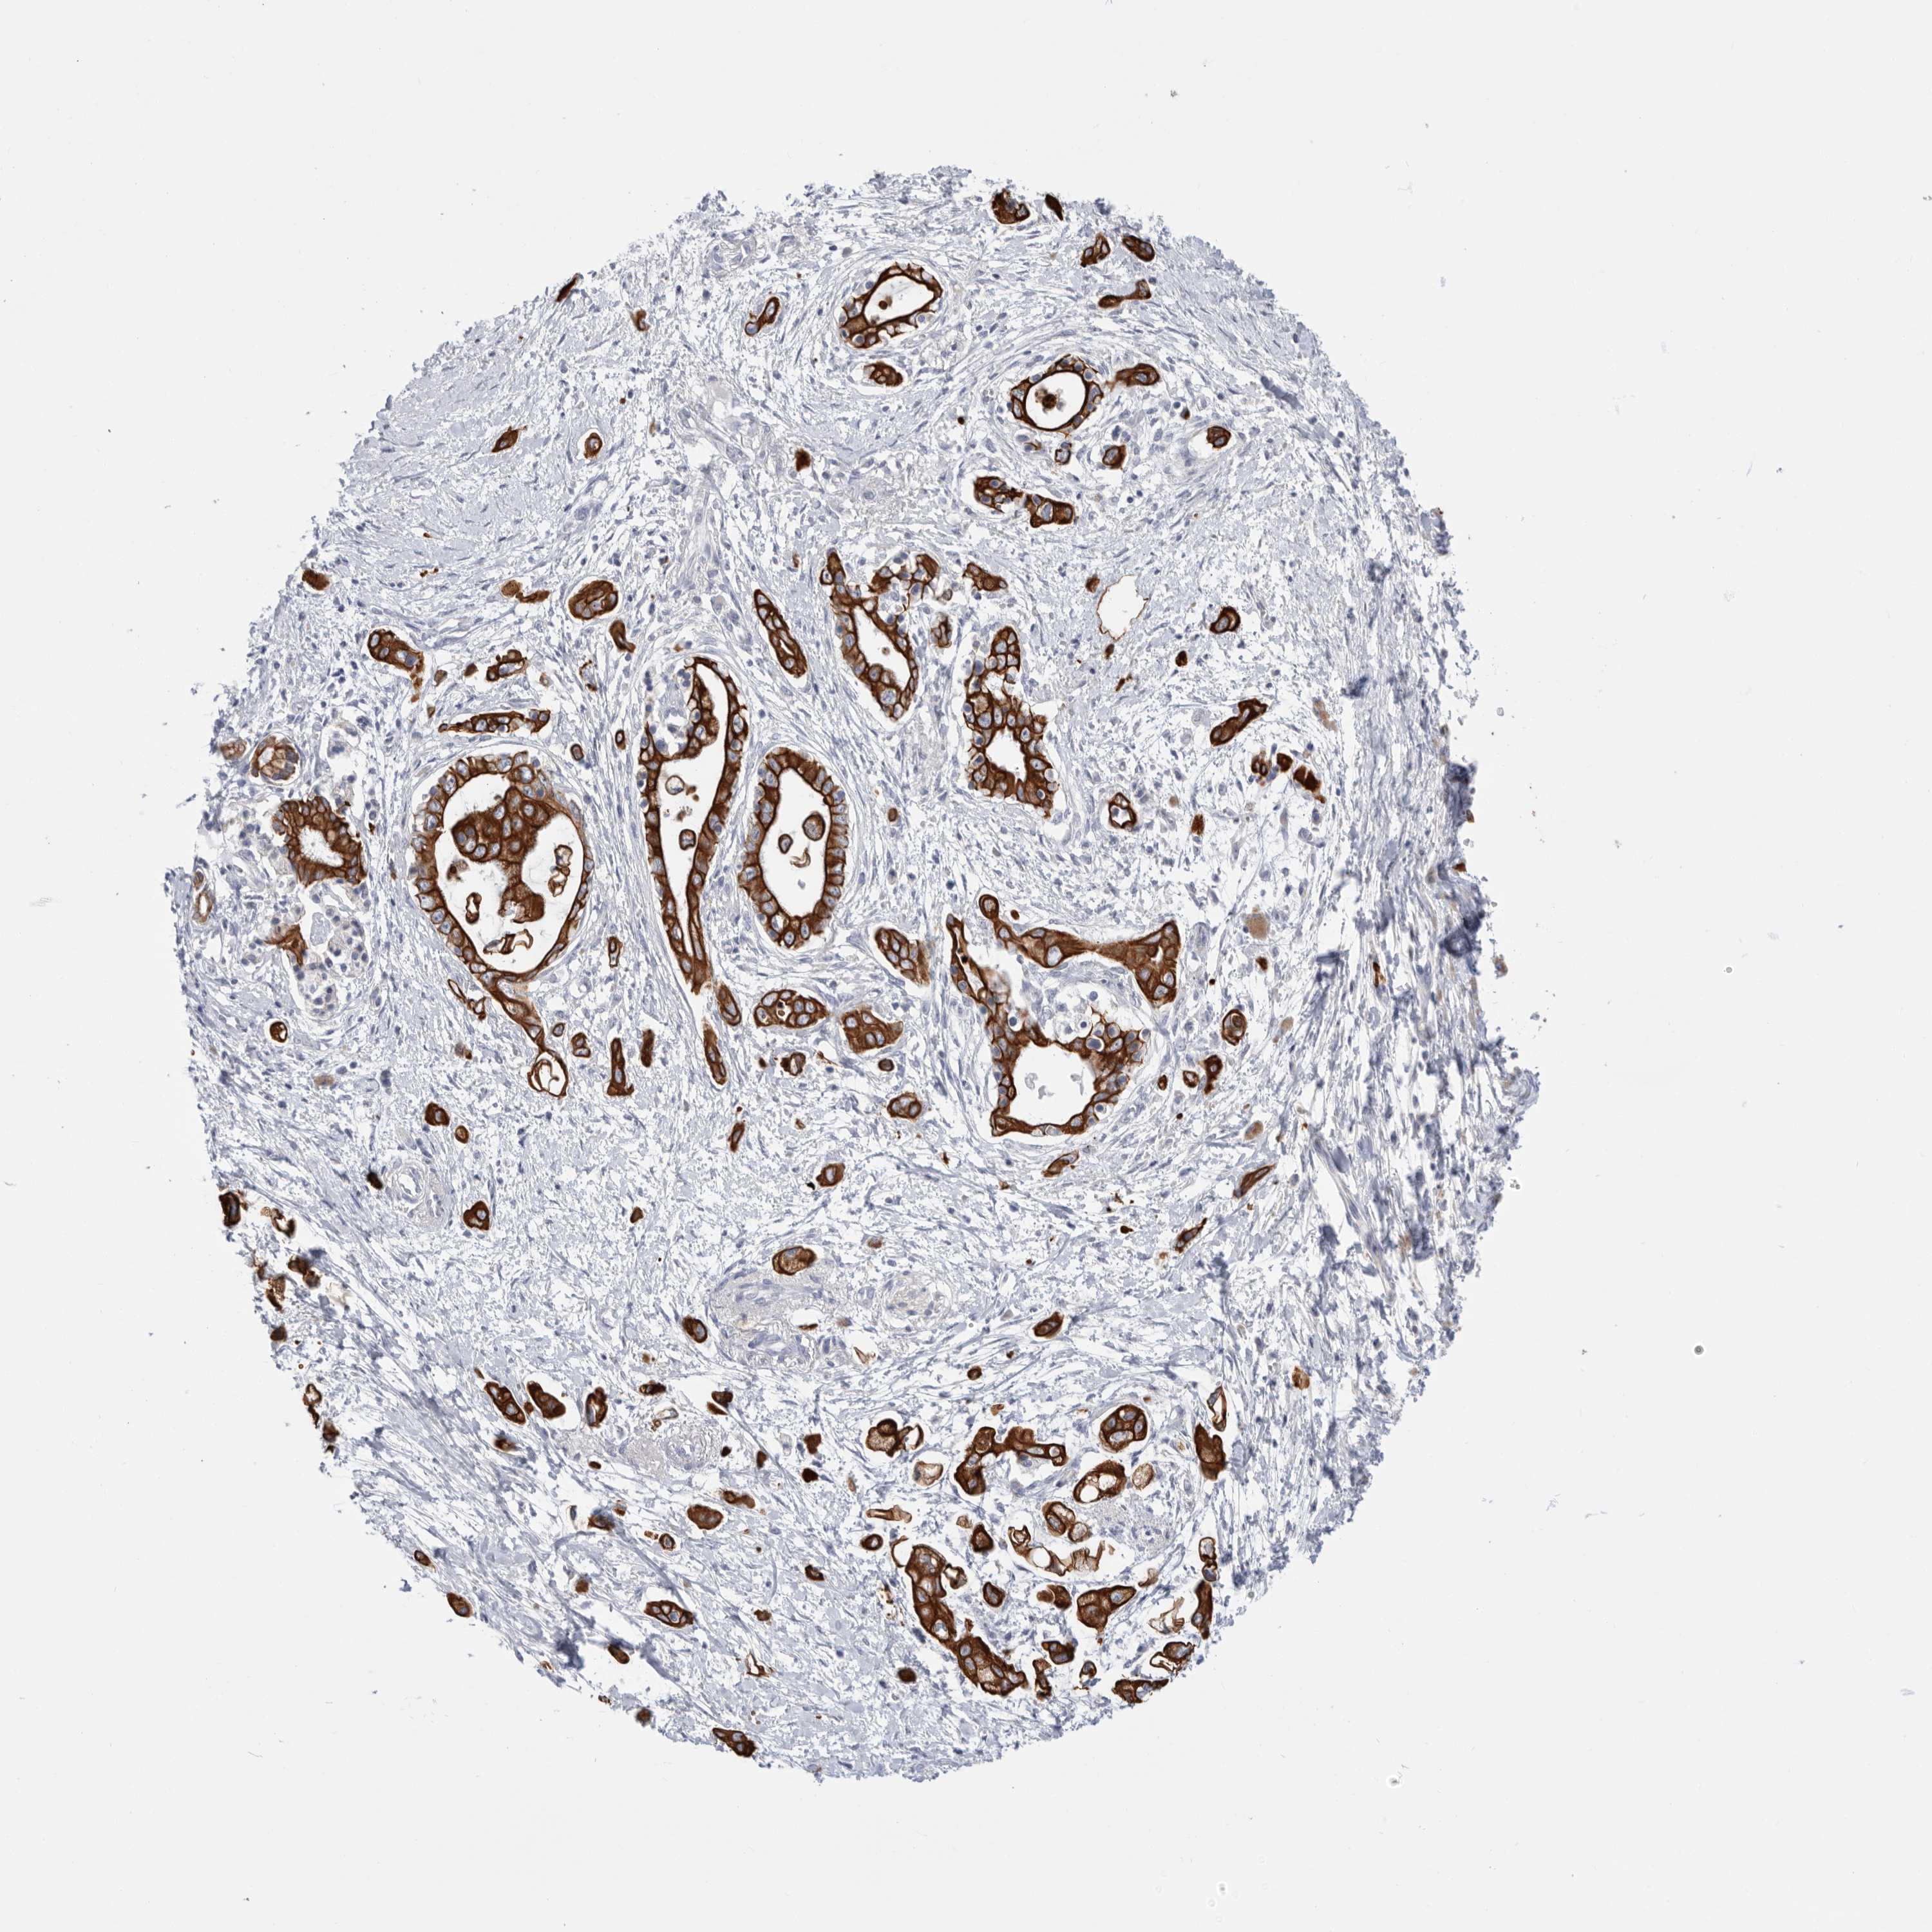

PANCREATIC CANCER - Protein expressioni

A mouse-over function shows sample information and annotation data. Click on an image to view it in a full screen mode. Samples can be filtered based on level of antibody staining by selecting one or several of the following categories: high, medium, low and not detected. The assay and annotation is described here.

Note that samples used for immunohistochemistry by the Human Protein Atlas do not correspond to samples in the TCGA dataset.

Antibody stainingi

Antibody staining in the annotated cell types in the current human tissue is reported as not detected, low, medium, or high, based on conventional immunohistochemistry profiling in selected tissues. This score is based on the combination of the staining intensity and fraction of stained cells.

Each image is clickable and will lead to virtual microscopy that enables deeper exploration of all samples and also displays staining intensity scores, fraction scores and subcellular localization as well as patient and tissue information for each sample.

Antibody HPA027124

Antibody HPA027130

Adenocarcinoma, NOS